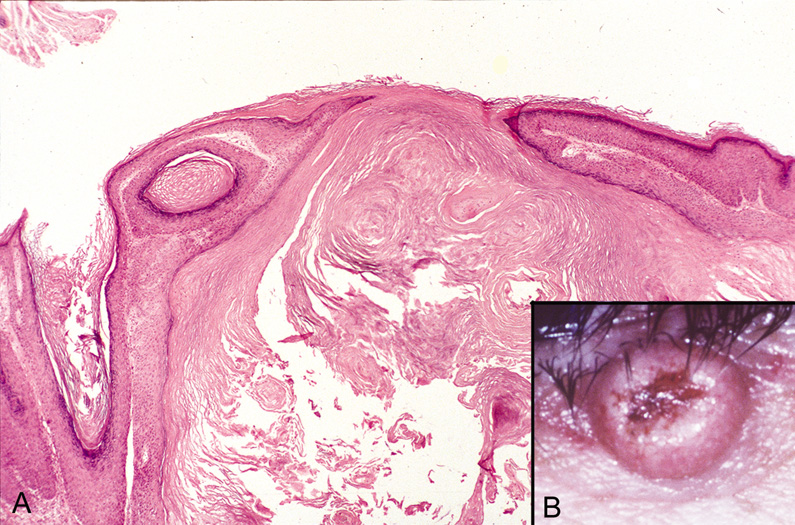

Dermoid Cysts

Dermoid cysts are usually present at birth and commonly occur around the eyes. They may be adherent to the periosteum. Dermoid cysts are believed to result from sequestration of skin and its appendages along embryonic lines of closure and, thus, are commonly found at the frontozygomatic suture.

Histologically, dermoid cysts are lined by epidermis possessing various mature appendageal structures (Fig. 22). These include hair follicles with terminal hairs, sebaceous glands, eccrine glands, and, occasionally, apocrine glands.

Fig. 22. A. Dermoid cyst shows hair follicle (h) and hair shaft (arrows) in cyst lumen. B. Dermoid cyst has skin appendages in cyst wall (arrow), is lined by stratified squamous epithelium, and contains desquamated keratin in its lumen (L). There is a granulomatous inflammatory infiltrate (g) due to rupture of cyst. (From Yanoff M, Fine BS: Ocular Pathology, 3rd ed. Philadelphia, JB Lippincott, 1989, 186.)